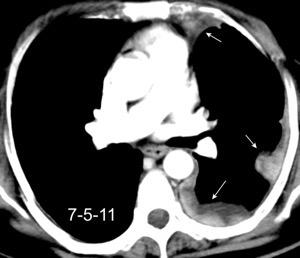

Carcinoma de mama con derrame pleural e implantes metastáticos

Makis W et al. Spectrum of Malignant Pleural and Pericardial Disease on FDG PET/CT. AJR. 2012